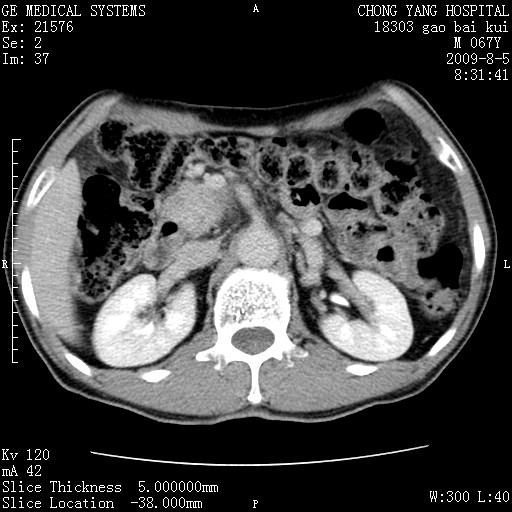

这个也过了,考虑胰腺钩突癌或壶腹癌,不除外胰管粘液乳头瘤伴胰管扩张,肝内胆管积气.

1)考虑胰头癌或壶腹癌并胰管扩张。2)肝外胆管扩张、积气,胆囊影未见;考虑术后改变。3)胃壁增厚?建议必要时行胃镜检查。

虑胰腺钩突癌或壶腹癌,不除外胰管粘液乳头瘤伴胰管扩张,肝内胆管积气.

考虑胰头癌并十二指肠受侵。